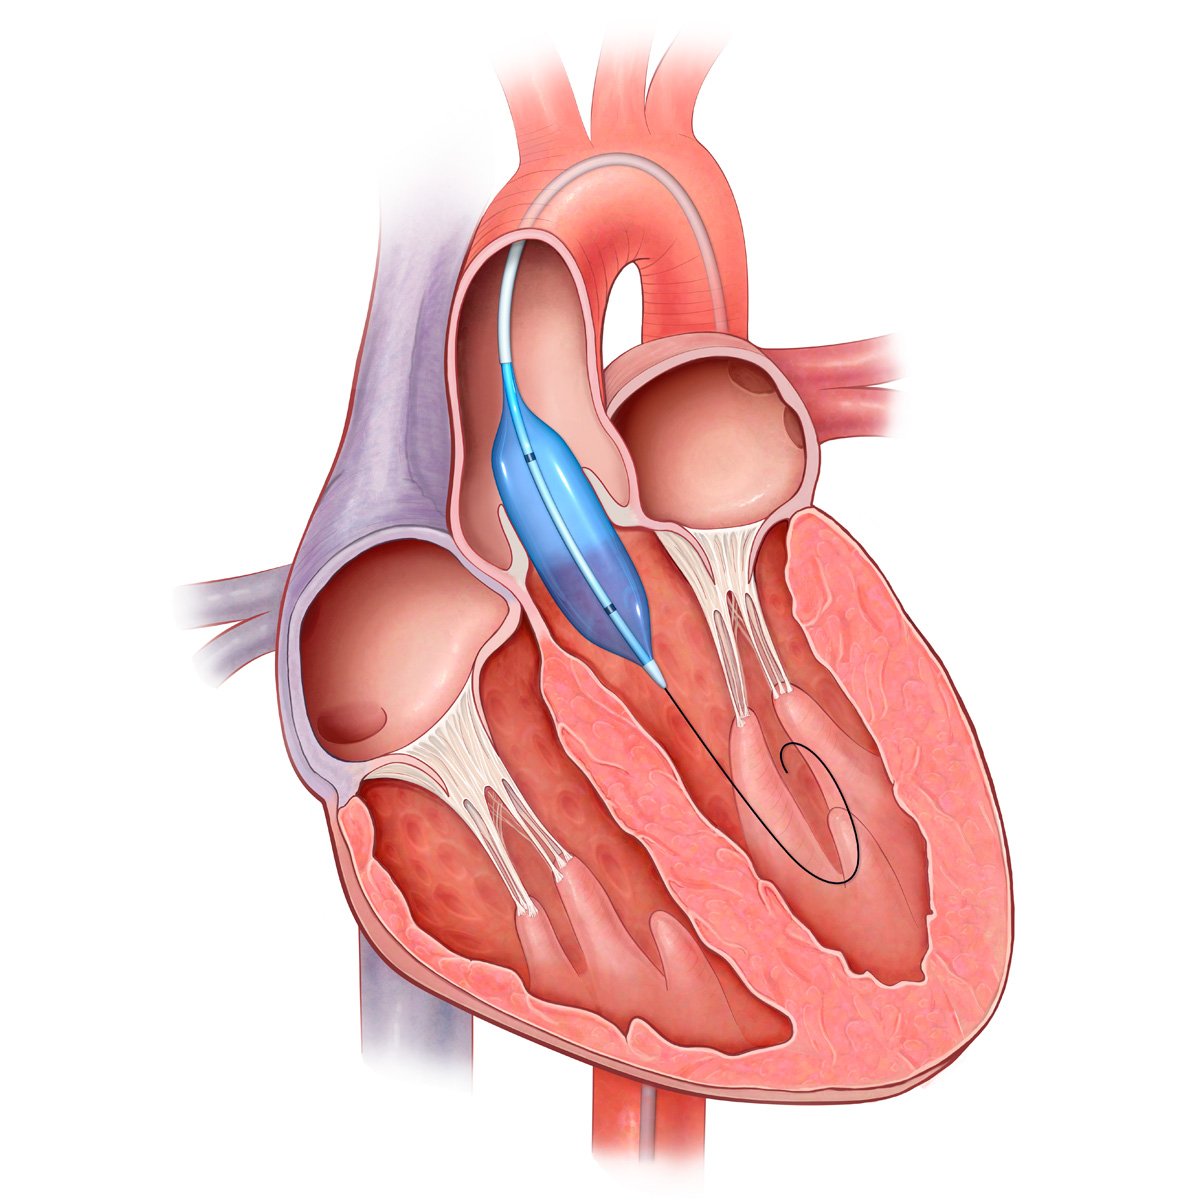

Пороки сердечно-сосудистой системы: виды и признаки